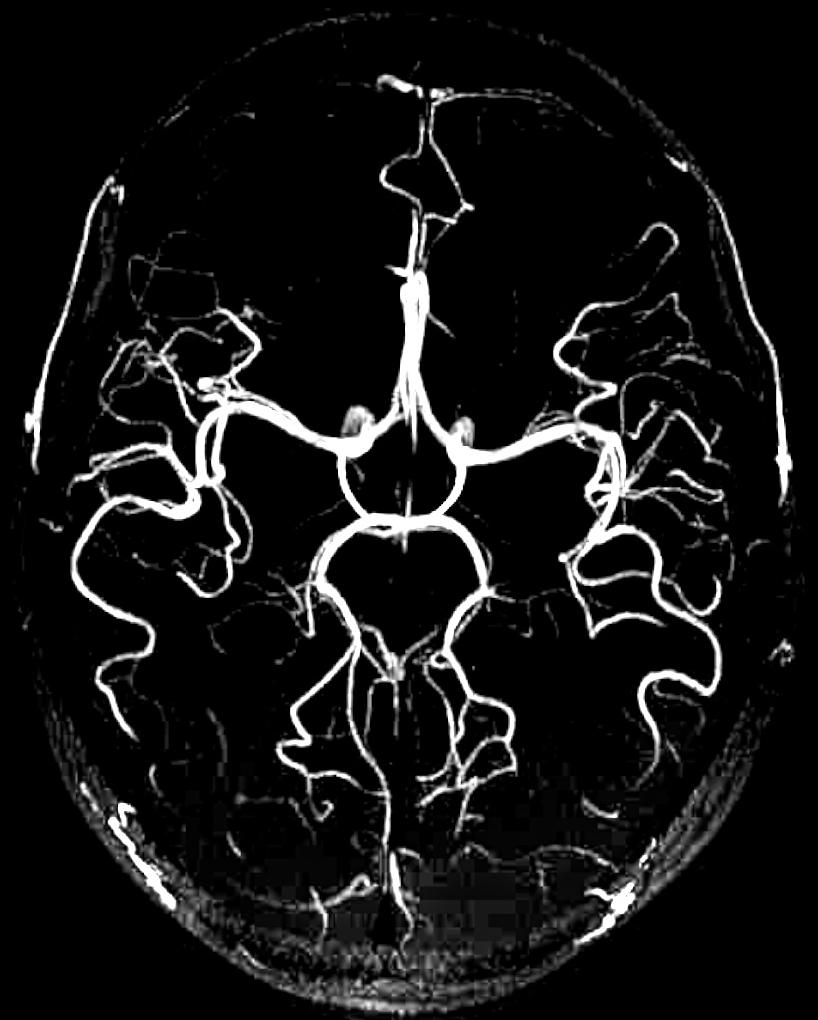

Pathology